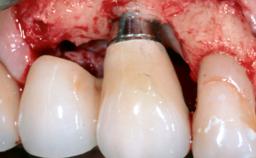

Late Presentation of Peri-Implant Mucositis Requiring Soft-Tissue Augmentation and Esthetic Crown Lengthening at Implant Site 11

Biological or technical complications around implant-supported prostheses place a significant burden on patients as well as the surgical and restorative team. Inflammation of the peri-implant soft tissues is often the first sign that something has gone awry. While there is never a good time for a complication, late presentation of inflammation in the soft tissues around a long-standing prosthesis triggers a period of research and review of the case in order to ascertain the treatment history and its possible contribution to the etiology of the situation. This becomes more complicated in situations where a patient has not received regular maintenance and clinical/radiographical examinations due to personal, financial, or professional reasons. When the complication occurs in the esthetic zone, the complexity of the situation expands exponentially, as the only acceptable outcome in the patient’s eyes will be the maintenance of the esthetics of the prosthesis.